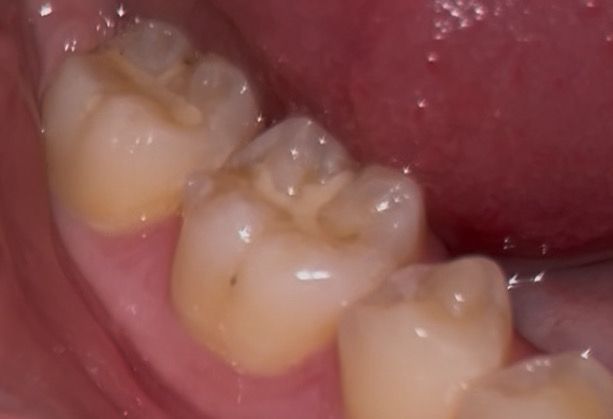

이정도 치아 깨진거 치료 받아야할까요? +충치

딱딱한거 씹다가 깨졌는데

가끔 뜨거운거 먹었을때시큰거리는 정도고

일상생활할때 불편한건 없습니다

1. 깨진거 치료 받아야할까요?

2. 저정도 깨짐은 어떻게 치료하나요? 아플까요?

2. 옆면에 있는 충치 상태도 좀 봐주세요 ㅠㅠ

사진으로 봤을 경우에 치아가 깨진 것보다 부분 부분 충치가 보이고 있습니다. 충치가 있는 부분엔 이물질이 남아 있게 되어 충치가 진행될 수 있으니 충치가 있는 부분은 치료를 해주는 것이 좋습니다.

깨진 정도가 크진 않으나 한번 깨졌던 치아는 그 부위가 씹을때 힘이 강하게 가해진다는 것이므로 또 추가적으로 깨질 우려가 큽니다. 전반적으로 상태 보고 레진으로 떼우거나 아니면 크라운을 씌워주면 좋을 것 같습니다.

옆면 충치 큰 편은 아닙니다.